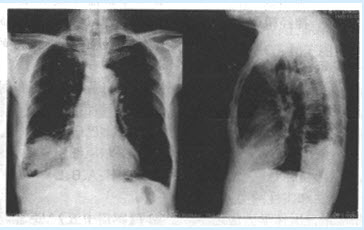

患者,男,72岁。咳嗽、咳痰、痰中带血1个月,头痛1周。患者1个月前无明显诱因下出现咳嗽、咳痰,痰多为白色黏液样带有血丝,无脓痰,平时活动后易出现气急、胸闷,患者抽烟50年,每天1包。查体:右下肺可闻及湿性啰音。抗感染治疗一周症状未见明显好转。患者X线平片如下图所示。

(单选题)该病变的部位是()

A:右肺中叶

B:右肺下叶

C:脊柱

D:右侧胸壁

E:肝

F:右上肺